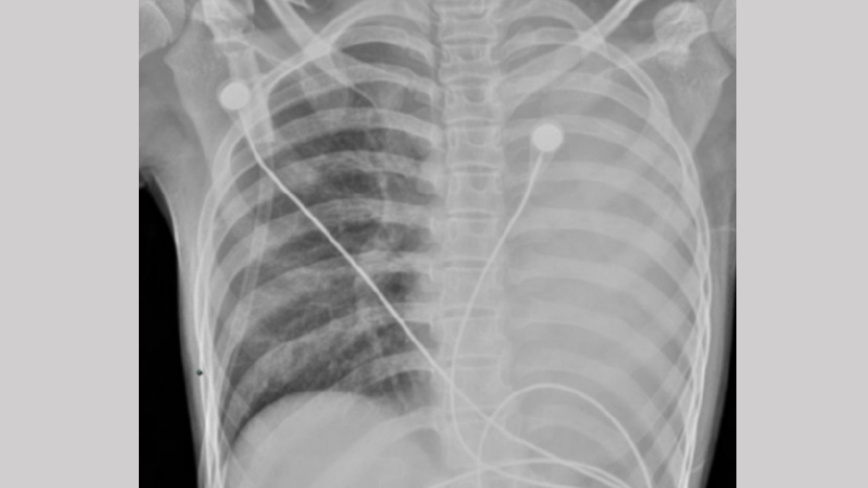

中國疫情嚴重 不少兒童白肺或病亡 民眾恐慌

浙江一名11歲男孩感染病毒後,一天之內就發展成了「大白肺」,被送進ICU急救。同時,出現大量兒童死亡病例,引發家長恐慌。

中國11歲男孩發病一天就「白肺」肺堵死喘不上氣

中國大陸各地流感疫情快速升溫,學校成疫情重災區,多地學校停課。近期,浙江一名11歲男孩小宇(化名)一天之內就發展到肺堵死、喘不上氣,引發「白肺」送進ICU。

中國疫情變異不斷 兒童感染幾小時右肺全白

中國流感疫情凶猛,多重病毒同時流傳,許多城市兒童醫院急診科是人滿為患,北京、天津和浙江等地,不少學校因班級大規模感染而緊急停課。